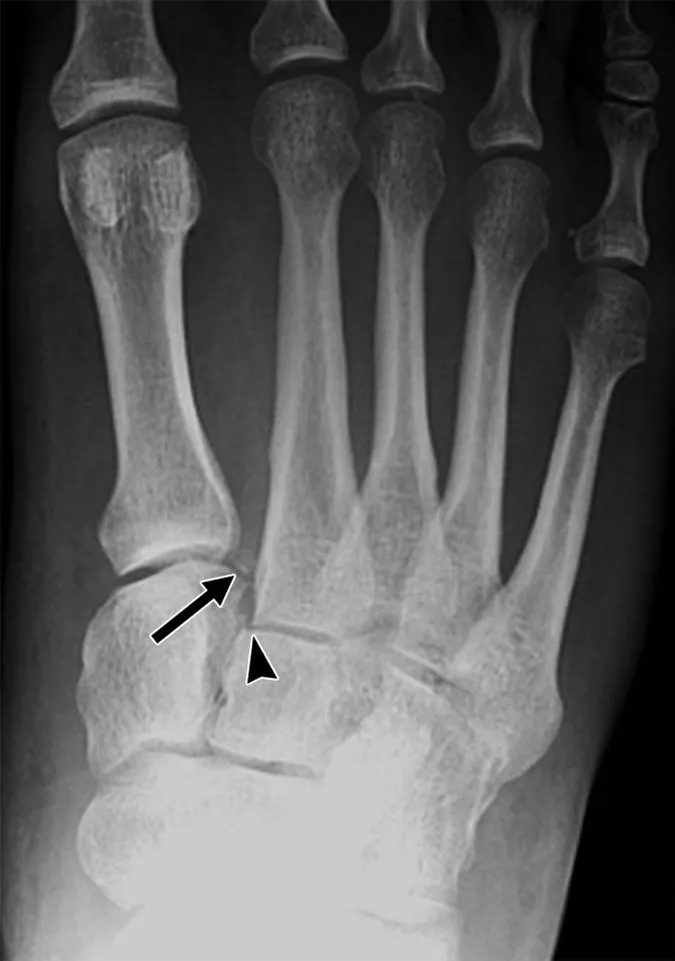

嚴(yán)格說骨裂屬于骨折中的一種,不過它和骨折還是有明顯的區(qū)別。與骨裂最接近的疾病是裂紋骨折,是一種閉合、穩(wěn)定、不完全性骨折。

骨折是人們在意外的情況下造成的現(xiàn)象,一般是由直接或者間接暴力或者是積累性勞損所造成的傷害,或者因病理性原因所致。骨折是骨皮質(zhì)的連續(xù)中斷而形成的一種現(xiàn)象,骨裂是骨折的一種形式。

而骨裂則是一種不完全性骨折,由于骨關(guān)節(jié)的連續(xù)性和完整性也同樣遭到了破壞,因此骨裂屬于骨折的其中一種。